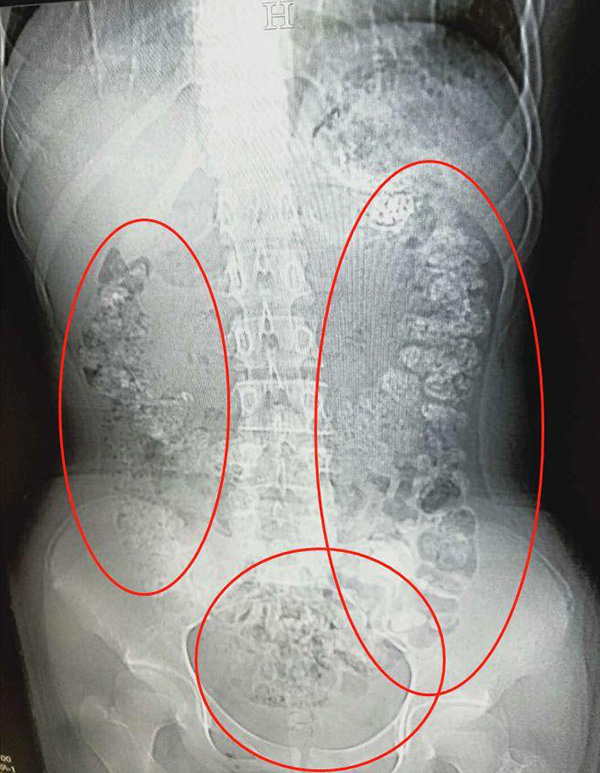

5月28日晚,浙江的小姑娘小沈(化名)在父母陪同下到浙江诸暨市人民医院急诊,说自己五天都没有排便,还肚子疼,也吃不下东西。医生见她肚子鼓鼓的,便安排了腹部CT,检查结果让医生大吃一惊:患者胃部、横结肠、升结肠、降结肠、乙状结肠,一直到肛门,全是一颗颗,圆圆的高密度阴影,看上起起码要百余颗——全都是没有消化的"珍珠”

全是一颗颗,圆圆的高密度阴影,看上起起码要百余颗——全都是没有消化的珍珠